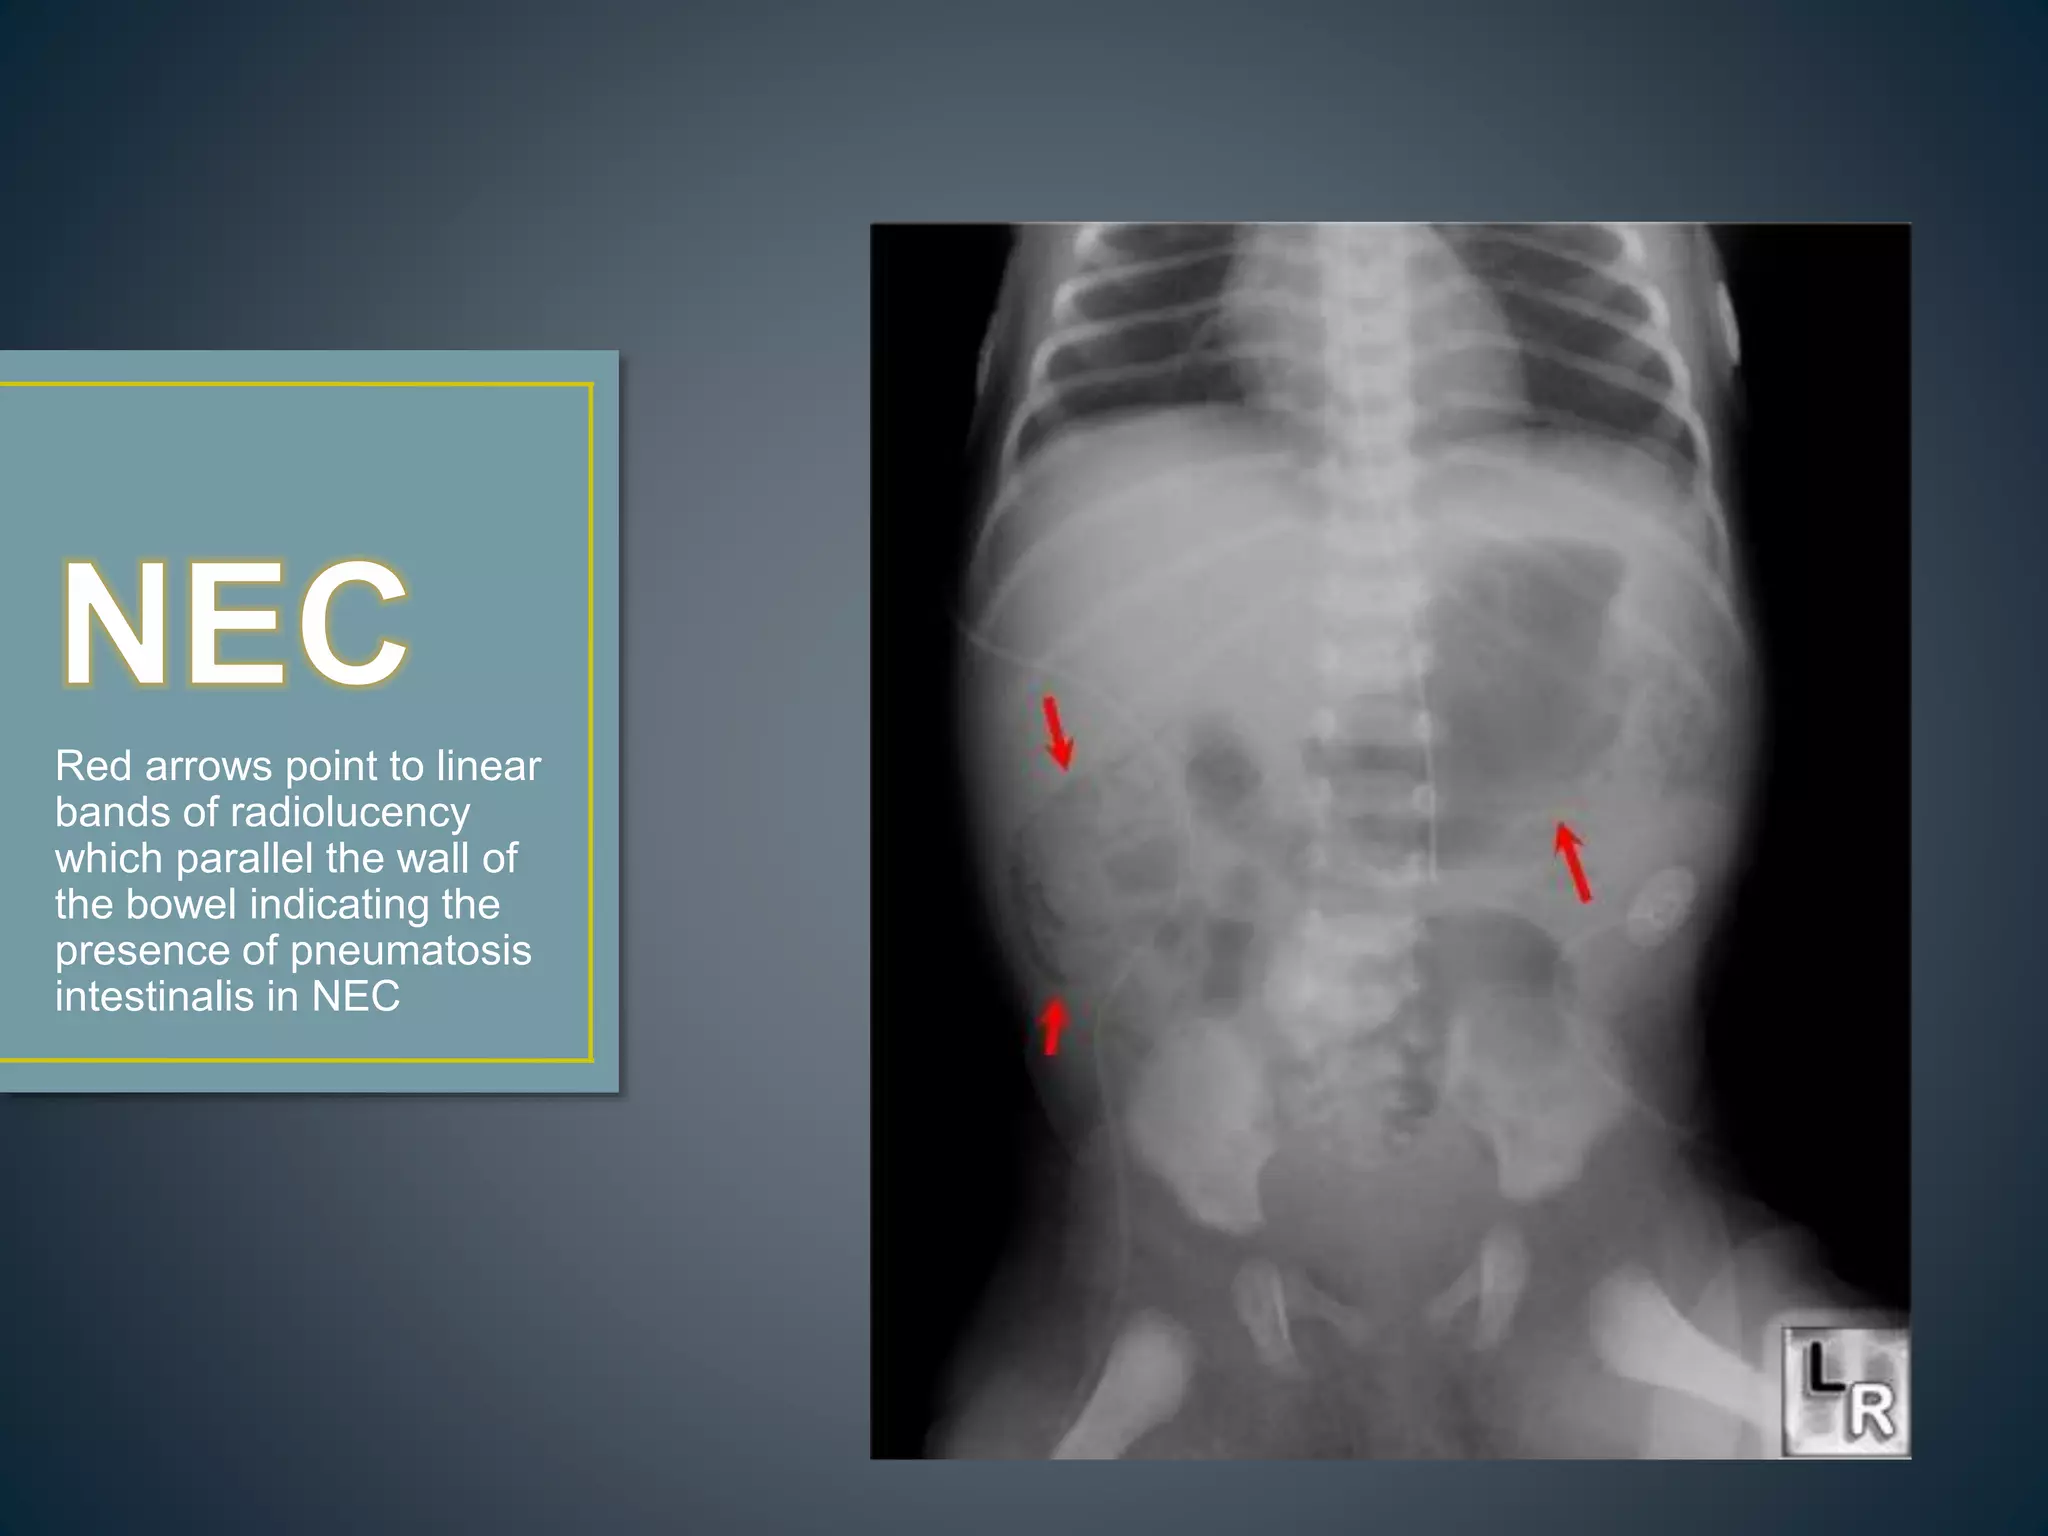

Red arrows point to linear

bands of radiolucency

which parallel the wall of

the bowel indicating the

presence of pneumatosis

intestinalis in NEC

Red arrows pointto linear bands of radiolucency which parallel the wall of the bowel indicating the presence of pneumatosis intestinalis in NEC